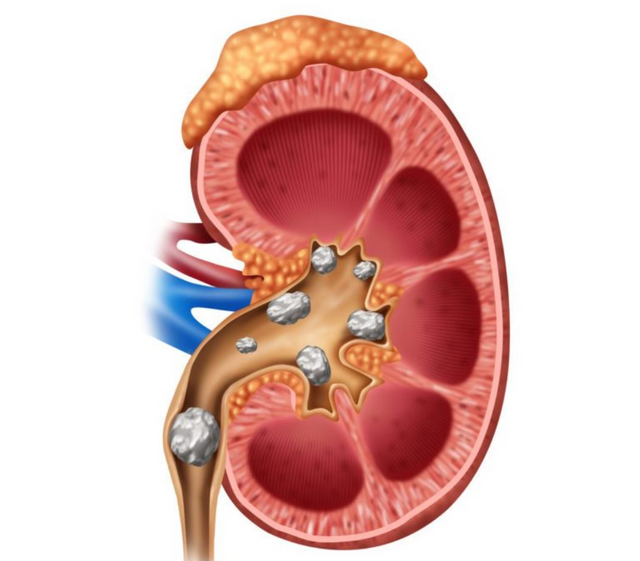

Los cálculos renales son pequeñas masas sólidas capaces de aparecer en el tracto urinario. También conocidas como nefrolitiasis, se forman cuando las sales y los minerales de la orina se concentran en cuantía y se cristalizan. Al cabo de un lapso de tiempo determinado como semanas o meses, dichos cristales pueden agrandarse y pasar a ser piedras.

Estas pequeñas masas solidificadas son capaces de medir desde una fracción, hasta varias pulgadas. Aquellos que cuentan con un diámetro de 0,2 pulgadas o menos de 5 mm (pequeños) son capaces de transitar por el tracto urinario con muy poco o nada de dolor. En contraposición, los cálculos grandes pueden llegar a ser muy dolorosos, impedir el flujo normal de la orina y provocar la presencia de sangre en la misma, así como otros síntomas. Aun así, la mayoría de los cálculos renales no causan daños permanentes.